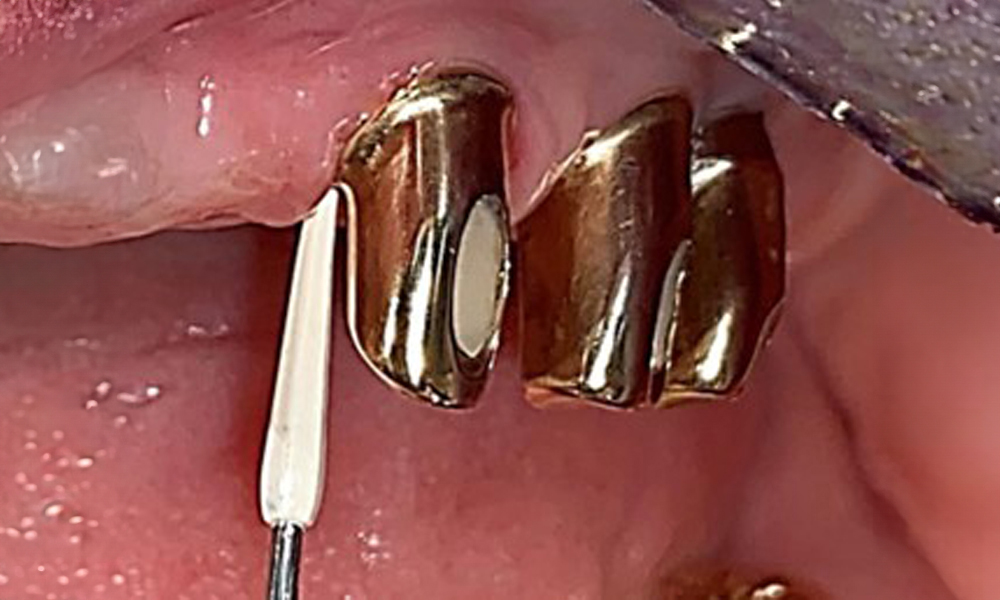

The patient was fitted with a combined removable maxillary telescopic prosthesis more than 25 years ago (Fig. 1, Fig. 2, Fig. 3) and is very happy with her dentures. The patient has an adequate fixed denture for the mandible (Fig. 4).

The dental findings are as follows: Combined removable implant and tooth-supported telescopic prostheses on implants 15, 13, 21, 23, 24, 25 and tooth 11 (Fig. 1, Fig. 2, Fig. 3). The patient was fitted with a fixed mandibular denture. Adequate bridges were present over 37 to 34 and 45 to 47 (Fig. 4), the crown margins were intact and there were no active caries. A composite filling with a marginal gap was present on tooth 43. There was mandibular gingival recession, exposing 1 to 3 mm of root surface. This also applies to 11.

Sonic/ultrasonic, or conventional manual instruments may be used to remove calculus and concretions present on the natural teeth (8). Titanium or plastic curettes (Fig. 10), or a plastic or PEEK attachment (Fig. 11) during ultrasonic treatment, should be used to remove mineralized plaque from implants to avoid damaging the implant surfaces.